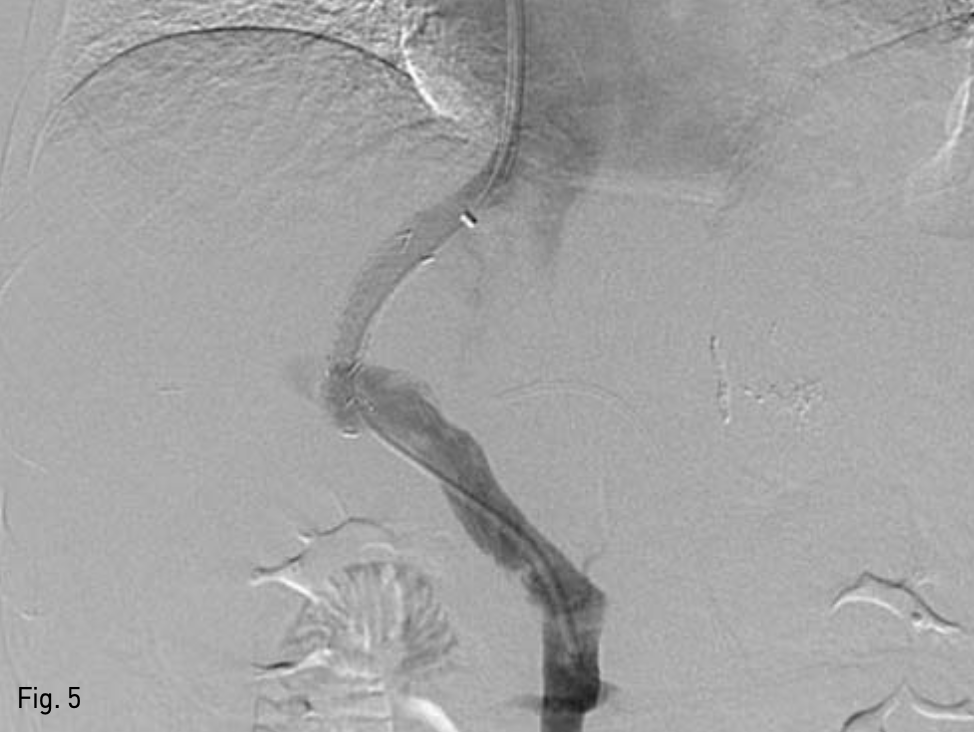

Fig. 5

Stent placement. 10mm x 3.5cm covered x 0.5 and 1.0cm bare metal stent; Niti-S TIPS Stent insertion was done.

복벽에 확장되어 있는 recanalized paraumbilical vein을 초음파 유도하에 천자하여(Fig. 3), 왼쪽 문맥 으로 5-Fr 카테터를 삽입하였다. 문맥조영술을 시행하여 간내문맥을 확인하였다. Right intrnal jugular vein을 천자하여 5-Fr 카테터를 삽입하여 오른쪽 간정맥 조영술을 시행하고 오른쪽 간정맥을 신택한다. 이후 recanalized paraumbilical vein을 통한 문맥조영술 을 roadmap으로 이용하여 16G Colapinto needle (Cook Inc, Bloominglon, IN, USA) 오른쪽 간문맥을 천자하였다(Fig. 4). 천자된 경로를 6mm x 4cm balloon (Mustang, Boston Scientific, Massachusetts, USA)을 이용하여 확장하고, 10mm x 5cm partially covered stent (Niti-s TIPS Stent, Tae Woong medical, Gyeonggi-do, Korea)를 간문맥과 중간간정맥 샛길에 삽입하였다. 이후 스테트가 펴지지 않은 부분을 펴기위해 10mm x 4cm balloon (Mustang, Boston Scientific, Massachusetts, USA)을 이용해 확장하였다. TIPS stent를 설치한 후 시행한 문맥조영술에서 식도정맥류를 보이지 않았고 stent를 통한 원활한 혈류를 확인 할 수 있었다(Fig. 5). 문맥의 평균압력이 시술 전 22mmHg에서 시술 후 14mmHg로 감소하였고, 최대 정맥문맥 압력차이가 16mmHg에서 1mmHg로 감소하였다.